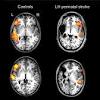

Babies get strokes too. Here's how their brains recover AUSTIN—Strokes are common in old age, but these devastating events also strike babies. That's likely because birth is stressful and particularly hard on the body's blood vessels and circulation.